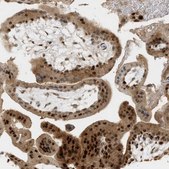

The Human Protein Atlas project can be subdivided into three efforts: Human Tissue Atlas, Cancer Atlas, and Human Cell Atlas. The antibodies that have been generated in support of the Tissue and Cancer Atlas projects have been tested by immunohistochemistry against hundreds of normal and disease tissues and through the recent efforts of the Human Cell Atlas project, many have been characterized by immunofluorescence to map the human proteome not only at the tissue level but now at the subcellular level. These images and the collection of this vast data set can be viewed on the Human Protein Atlas (HPA) site by clicking on the Image Gallery link. We also provide Prestige Antibodies® protocols and other useful information.

- IHC tissue array of 44 normal human tissues and 20 of the most common cancer type tissues.